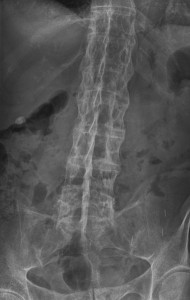

Ankylosing Spondylitis